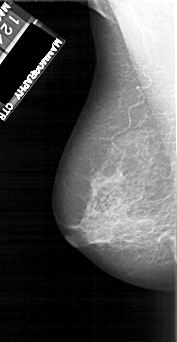

A_1118_1.LEFT_CC

LEFT_CC LINES 4966 PIXELS_PER_LINE 2431 BITS_PER_PIXEL 12 RESOLUTION 43.5 NON_OVERLAY